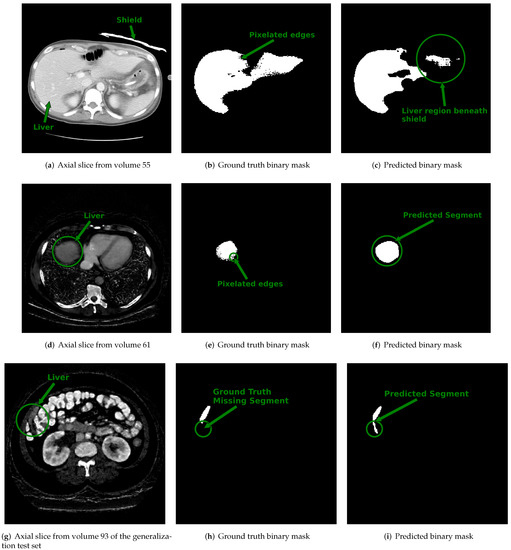

Figure 6. Displayed are example cross sectional axial slices with ground truth annotations and predicted contours from 3D u-net. Top Row: (a) Axial slice from single energy CT (SECT) scan of a patient within the CT-ORG training dataset shows an attenuating shield placed over segment 2 of the liver. (b) The ground truth binary image provided for the slice shown in (a) has pixelated edges pointed to by the arrow. (c) The output predicted by the 3D u-net for the slice in (a). The circled region pointed to by the arrow shows the area under the shield where the 3D u-net under-segmented the liver. Middle Row: (d) The synthetic dual-energy CT (synth-DECT) material density iodine (MDI) slice from a patient in the held-out test set. The liver is circled and pointed to by an arrow. (e) The ground truth binary image provided with the CT-ORG dataset for the slice shown in (d) also has pixelated edges that are circled and pointed to by the arrow. (f) The output predicted by the 3D u-net is circled and pointed to by the arrow. It incorporated the entire extent of the liver, without any pixelation. Bottom Row: (g) An axial slice from a patient scan in the generalization test set. The circled area and arrow point the portion of the liver at the margins of the liver. (h) The ground truth slice for the image shown in (g) does not contain a portion of the liver. The circle and arrow point to the segment of the liver missing from the ground truth annotation. (i) The predicted output by the 3D u-net. The circle and arrow point to the segment of the liver that was successfully identified by the 3D u-net, but was missing from the ground truth annotation shown in (h). The top row shows the impact of noise and beam hardening arising from the shield’s on the predictions of the 3D u-net. Several scans in the training dataset had ground truth contours with pixelated edges, missing segments of the liver, or inclusion of non-liver tissue, as shown in this figure.

Examples of slices from scans within the dataset with the lowest DSC values (i.e., DSC < 0.8) are displayed in Figure 6. Figure 6a shows the center slice of the liver, which is where the liver occupies around 50% or more of the abdominal space. In contrast, at the start and end slices, the liver tissue occupies a minor proportion of the abdominal area, as illustrated in Figure 6d,g. We suspect that the reduced DSC scores at the start and end slice locations are a byproduct of the small size of the liver tissue relative to the background and partial volume averaging artifacts that falsely reduce or increase the pixel intensity value of border pixels. Consequently, the class imbalance and artifacts at the margins of the scan may increase the likelihood of misclassifying pixels.

Additional factors that contributed to the lower DSC score are also illustrated in Figure 6. In Figure 6a, we found a case in which a bismuth or lead shield was placed over the patient’s abdomen during the scan. The shield attenuates X-rays, causing beam hardening and streak artifacts, as well as increasing noise in the organs beneath it. In addition to the shield, the ground truth annotation provided by the dataset organizers shown in Figure 6b contained pixelated edges. As shown in Figure 6c, the combined effect caused the 3D u-net to undersegment the portion of the liver directly under the shield. Figure 6d–f show an example slice with its ground truth contour that contains pixelated edges and the predicted output of the 3D u-net. In this case, the reduced DSC score was not a result of over or under segmentation by the 3D u-net but was, instead, due to the differences arising from the pixelation in the ground truth and lack thereof in the predicted output. In another example shown in the final row of Figure 6g–i, the reduced DSC score for this case was because the ground truth annotation displayed in Figure 6h did not outline the entire segment of the liver. However, as illustrated in Figure 6i, the predicted output of the 3D u-net included the full extent of the liver. Several scans in the CT-ORG dataset had ground truth annotations that were rough outlines of the liver or consisted of pixelated edges [45]. Despite imprecise ground truth contours, the 3D u-net trained using synth-DECT MDI scans was still able to predict the complete extent of the liver tissue for many patient scans.